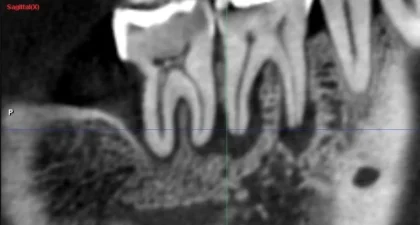

これは一般的なレントゲン写真とCTの部分的な画像です。

どうですか?レントゲンには写ってこないのですが、CTではハッキリと根の周囲に黒い影が見えます👀

これは2次元のレントゲンでは周りを厚い骨で囲まれている為に、根の病気が写らないのです。

治療する上で診断がとても大事なので、根管治療、インプラント治療、親知らずの抜歯ではCT撮影をする場合があります。

CTの断面図